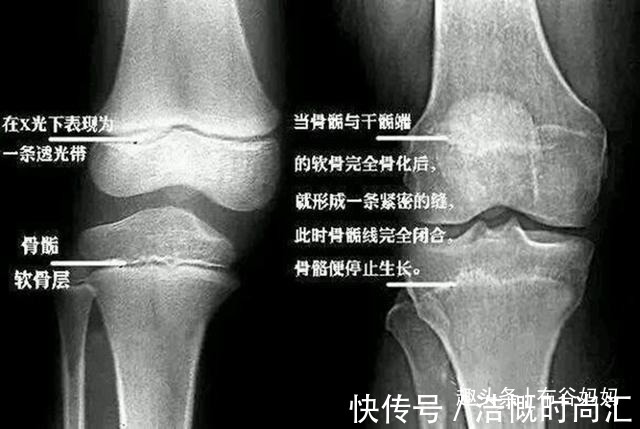

殊不知,孩子性早熟并不只是“成长提前了”这么简单,还会带来一系列危害。比如提前发育的外观,会让孩子觉得自己跟同龄人不一样,从而有自卑、羞耻感等心理。另外,性早熟还会让骨龄提前,引起骨骺线提前闭合,导致孩子达不到遗传身高。